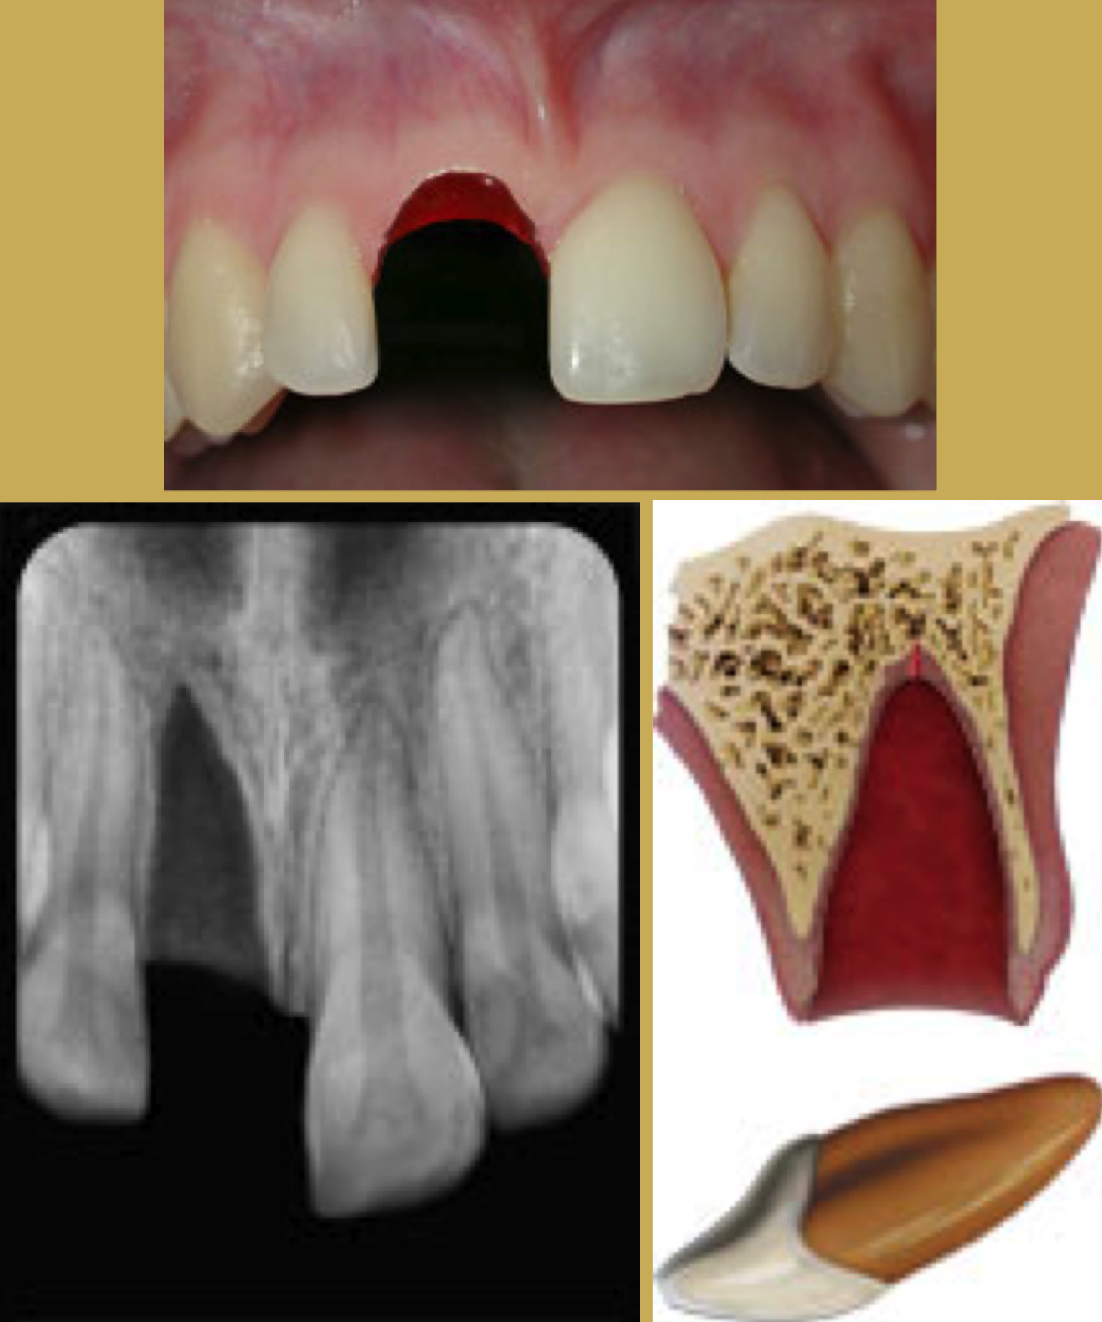

Fig 3. Images of Intrusion

Figure 3

Tooth Intrusion

Tooth intrusion occurs when the tooth has been driven into the alveolar process due to an axially directed impact (Figure 3). This is the most severe form of displacement injury. Athletes with intrusively luxated teeth should be immediately removed from play and transported to a sports emergency dentist.44

Pulpal necrosis occurs in 96% of intrusive displacements and is more likely to occur in teeth with fully formed roots. Immature root development will usually mean spontaneous re-eruption. Mature root development will require repositioning, surgery, and splinting or orthodontic extrusion. Treat relatively quickly since the pulp usually becomes necrotic - this can be treated with temporary filling of calcium hydroxide paste followed by root canal therapy.